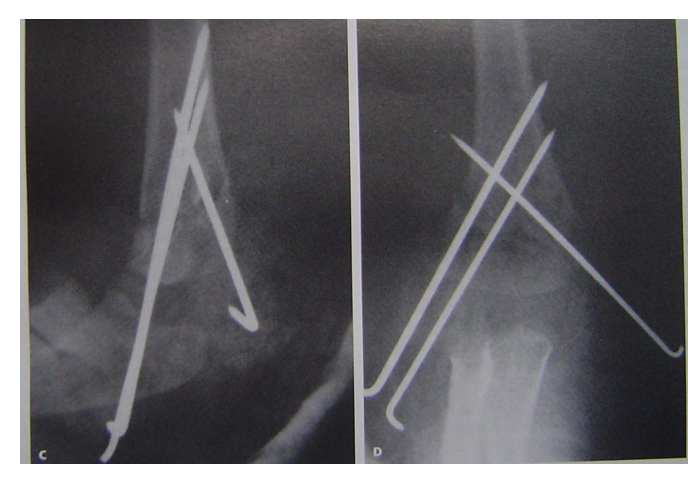

屈曲型伸直复位,伸直固定是方法之一。但石膏容易滑脱另一方法,伸直复位后屈曲肘关节,向后推挤维持复位,然后经皮克氏针固定。A、B术前x线片C 、D 手法复位 E 克氏针固定后